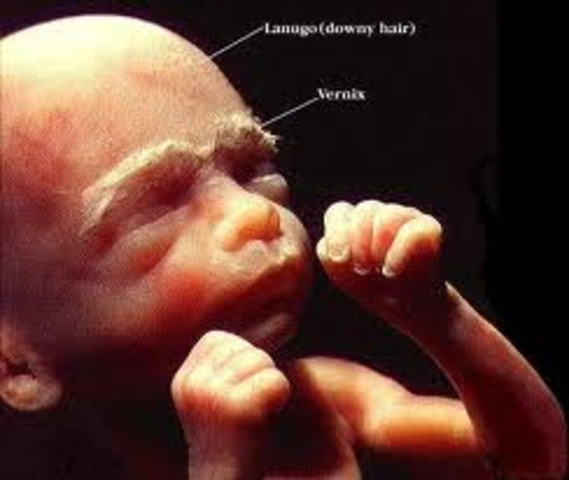

Mom: The mom will start feeling the baby moving, the increasing of the belly may start affecting posture.

Baby: About 6 1/2 inches. Hair, eyelashes, and eyebrows appear. Teeth are continuing to develop, while organs are maturing. The baby is becoming more active.